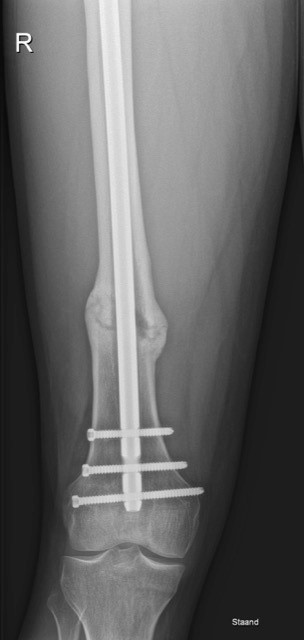

Dit is een fractuur van het bovenbeen. Jonge mensen lopen dit op door een zwaar trauma, ouderen of mensen met ziek bot kunnen dit bij een banale val oplopen.

De behandeling is steeds heelkundig en quasi altijd met een nagel die in het dijbeen zelf wordt ingebracht via een kleine insnede aan de zijkant van het bovenbeen. Die nagel wordt daarna met enkele schroeven boven en onder de breuk gefixeerd.

In het algemeen mag de patiënt na de operatie onmiddellijk steunen op het geopereerde been. De genezing van dit bot duurt meestal een drietal maanden.